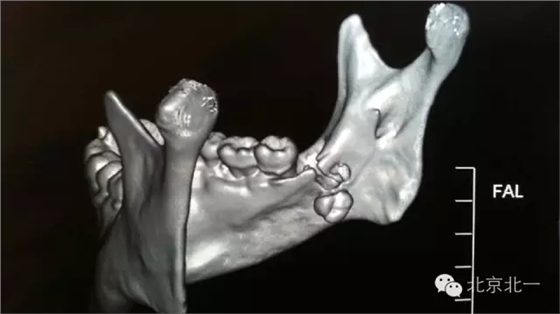

圖二:CBCT掃描重建清晰看到舌側(cè)骨板骨折,牙根位于舌側(cè)。而不是進(jìn)入下牙槽神經(jīng)管。

圖三:正面照